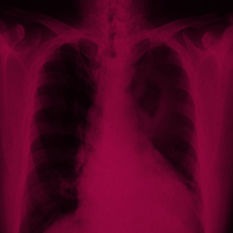

מסתמן: נמצאה תרופה יעילה לסרטן הריאה